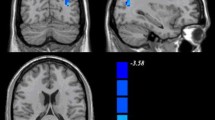

The whole-brain analysis of the whole-range degree centrality network revealed no significant genotype or diagnosis effects. However, significant genotype × diagnosis interactions on DC were found in the left inferior temporal gyrus (ITG) and bilateral middle temporal gyrus (MTG; GRF corrected p < 0.001, two-tailed; see Fig. 1A and Table 2). We then did the Post-hoc analysis for the genotype effect in ADHD and healthy controls separately. The analysis further revealed that the left ITG and bilateral MTG exhibited significantly higher DC values in the ADHD subjects with the DRD4 2R genotype (p < 0.05). Howerver, we observed significant lower DC values for the left ITG and a lower trend for bilateral MTG in the HC group with DRD4 2R (see Fig. 1B).

Diagnosis-by-genotype interactions on DC (Whole-Range). A Two-way ANCOVA revealed significant diagnosis by-genotype interactions on DC in the bilateral middle temporal gyrus (MTG), left inferior temporal gyrus (ITG). The color bar represents the statistical significance threshold (F-score). Multiple comparisons were conducted by Gaussian Random Field (GRF) theory (voxel significance: p < 0.001, cluster significance: p < 0.05). B The bar graphs depict post-hoc pairwise comparisons in the regions showing significant diagnosis-by-genotype interactions. The data were expressed as the mean (M) ± standard error (SE). DC, degree centrality; HC, healthy control; and ADHD, Attention-deficit/hyperactivity disorder. N.S, Non-significant. *p < 0.05; **p < 0.01